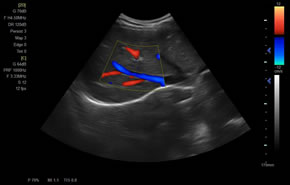

> 彩色血流量圖(CDE)

廣泛適用于腹部、婦產(chǎn)科、心臟、小器官、乳腺、肌骨及外周血管等諸多方面的診查,讓您在臨床超聲診斷應(yīng)用領(lǐng)域得心應(yīng)手,綻放異彩。